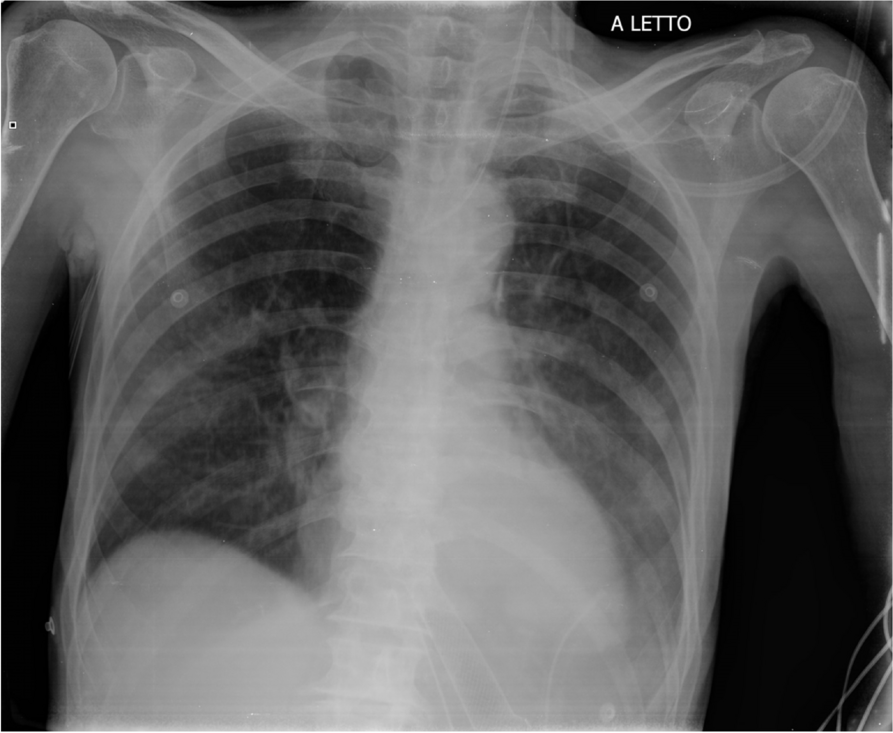

In this specific case, the patient, affected by L. Pneumophila, presented a PO2/FiO2 ratio between 100mmHg and 200mmHg, giving rise to a moderate ARDS panel according to Berlin Criteria (Image 1).

For this reason, we decided to use a non-invasive periprocedural ventilation mode, specifically the High Flow Nasal Cannula (HFNC), to reduce the risk of postoperative pulmonary complications due to invasive ventilation through endotracheal intubation (ETI).

The parameters set during the entire procedure remained stable: Flow 60 L/min, FiO2 100%, Temperature 37 °C.

The approximate duration of the procedure is 25 minutes. The patient's vital parameters are stable for all the duration of the intervention, with a SpO2 > 95%, and a MAP > 70 mmHg.

After the procedure, the patient is returned to the Intensive Care unit where he has completed the course of antibiotic therapy, with a progressive reduction of the need for oxygen therapy.

Airway management in patients with L. pneumophila can be a problem, aggravated by a series of additional risks related to ETI, such as pulmonary damage from mechanical ventilation, contamination of the ventilator, delayed weaning and an increase in hospital stay days. The use of HFNCs in endoscopic procedures allows to avoid these risks, eliminating the operating field conflict with the surgical procedure and guaranteeing a higher oxygen saturation compared to other oxygenation devices.

Image 1 (abstract A9).

See text for description